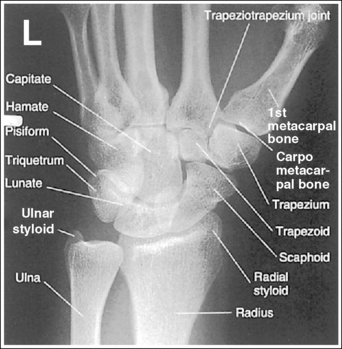

See Figure 4-34 and Box 4-12.

The wrist has been externally rotated to a 45-degree PA oblique projection. The trapezoid and trapezium are demonstrated without superimposition, and the trapeziotrapezoidal joint space is open. The scaphoid tuberosity and waist are demonstrated in profile. Only a small degree of trapezoid and capitate superimposition is present.

• To accomplish a PA oblique wrist projection, begin with the wrist in a PA projection, with the humerus and the forearm on the same horizontal plane. Externally rotate the hand and wrist until the wrist forms a 45-degree angle with the IR (Figure 4-35). When judging the degree of wrist obliquity, it is best to view the wrist and not the hand. The obliquity of the hand and wrist are not always equal when they are rotated, especially if the humerus and forearm are not positioned on the same horizontal plane for the image.

• Determining the accuracy of wrist obliquity. On a PA wrist projection (see Image 39), the trapezoid and trapezium are superimposed. Placing the wrist in a 45-degree externally rotated PA oblique projection draws the trapezium from beneath the trapezoid, providing clear visualization of both carpal bones and the joint space (trapeziotrapezoidal) between them. The PA oblique projection also rotates the scaphoid tuberosity and waist into profile. The relationships between the trapezoid and trapezium and the trapezoid and capitate are used to discern an accurate PA oblique wrist projection. If the wrist is underrotated, the trapezoid and trapezium are superimposed, the trapeziotrapezoidal joint space is obscured, and the trapezoid demonstrates minimal capitate superimposition (see Image 40). If wrist obliquity is more than 45 degrees, the trapezium demonstrates minimal trapezoidal superimposition, the capitate is superimposed by the trapezoid, and the trapeziotrapezoidal joint space is obscured (see Image 41).

The second CM and the scaphotrapezoidal joint spaces are demonstrated.

• For the PA wrist projection, the CM joints are opened by flexing the hand until the metacarpals are at a 10- to 15-degree angle to the IR. When the hand and wrist are placed in obliquity, the same metacarpal tilt must be maintained to open the second CM and scaphotrapezoidal joint spaces. If the distal second metacarpal is positioned too far away from the IR, a portion of the metacarpal (MC) superimposes the trapezoid, closing the second CM and scaphotrapezoidal joints (see Image 40).

The long axes of the third metacarpal and midforearm are aligned with the long axis of the collimated field. The scaphoid tuberosity and waist are demonstrated in profile and are not positioned directly next to the radius.

• If the long axes of the third metacarpal and midforearm are aligned with the long axis of the collimation field, the patient's wrist is placed in a neutral position. Radial deviation increases the foreshortening of the scaphoid, preventing visualization of the scaphoid tuberosity and waist, and positions the scaphoid directly next to the radius (see Image 42). Ulnar deviation decreases scaphoid foreshortening (see Image 43).

The distal radius is demonstrated without foreshortening. The anterior and posterior margins of the radius are nearly superimposed.

• The distal radial carpal articular surface is concave and slants approximately 11 degrees from posterior to anterior when the radius and ulna are positioned parallel with the IR. Because the forearm is positioned parallel with the IR for a PA oblique wrist projection, the slant of the distal radius causes the posterior margin to be projected slightly (0.25 inch or 0.6 cm) distal to the anterior radial margin, obscuring the radiocarpal joints.

The ulnar styloid is in profile at the far medial edge.

• The position of the humerus and elbow determines the placement of the ulnar styloid. The ulnar styloid is demonstrated in profile when the patient's humerus is abducted to align the humeral epicondyles perpendicular to the IR and place the elbow in a lateral position. If the humerus is not abducted to this degree, the ulnar styloid is no longer demonstrated in profile.

The carpal bones are at the center of the exposure field. The carpal bones, one fourth of the distal ulna and radius, and half of the proximal metacarpals are included within the collimated field.

• The wrist joint is located at the base of the first proximal metacarpal. To obtain a PA oblique projection of the carpal bones with the least amount of distortion, place a perpendicular central ray at this level and centered with the midwrist area. Open longitudinal collimation to include half of the metacarpals. Transversely collimate to within 0.5 inch (1.25 cm) of the wrist skin line.